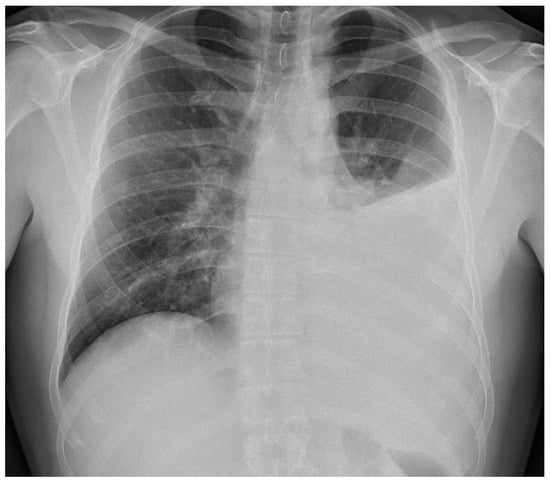

X-ray and CT scans of the chest were performed. The left lung’s lower lobe infiltrates and the right lung’s upper lobe interstitial changes (most probably of an inflammatory nature) were shown, as well as a small amount of fluid in the left pleural cavity (Figure 3 and Figure 4). Several tests were also performed to determine the etiology of the pneumonia. However, blood cultures, an antigen test for SARS-CoV-2, urine tests for Streptococcus pneumoniae, Legionella pneumophila, Cryptococcus sp., and Mycobacterium tuberculosis antigens, and an HIV screening test were all negative. In the following days, empirical antibiotic therapy with ceftriaxone and vancomycin was continued. A rapid improvement in the patient’s clinical condition was observed, as well as a significant decrease in the levels of inflammatory markers. On 22 August 2022, the patient was discharged home in good general condition.

Figure 3. Left lung lower lobe infiltrates are shown, as well as a small amount of fluid in the left pleural cavity at X-ray scan.

In this paper, we posed the question of whether there is a possible link between the initial infection and the subsequent occurrence of pulmonary disorders in the patient. Monkeypox viral pneumonia is one of the more commonly described complications of this disease in humans and can be associated with significant mortality [7,8,9,10,11]. Goff et al. published the results of an animal study (on primates), which concluded that monkeypox pneumonia can be lobular or interstitial pneumonia of viral etiology or can be caused by bacterial superinfection [10]. In the case we described, pneumonia occurred after the symptoms of the initial infection had already resolved and most likely was of bacterial etiology. Although it was not possible to identify any specific pathogen, bacterial etiology is supported by the overall clinical picture and, above all, the rapid resolution of symptoms after the administration of antibiotics. However, we cannot exclude the superposition of viral and bacterial pneumonia (in particular, bacterial superinfection of a primary viral infection). This possibility may be indirectly indicated by the heterogeneous radiological picture. In X-ray and CT scans, inflammatory lesions were visible in both lungs. However, while in the left lung, they were described as lobular pneumonia, in the right lung, there was an area of likely interstitial inflammatory lesions. It should be mentioned that the literature indicates that bacterial superinfection can exacerbate the symptoms of monkeypox viral pneumonia [10,12].